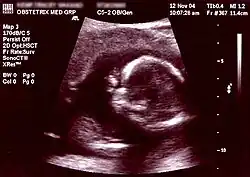

Ultrasonography is an example of a non-invasive diagnostic prenatal test.

Non-invasive Ultrasound detection Commonly dating scans (sometimes known as booking scans or dating ultrasounds) from 7 weeks to confirm pregnancy dates and look for multiple pregnancies. The specialised nuchal scan at 11–13 weeks may be used to identify higher risks of Downs syndrome. Later morphology scans, also called anatomy ultrasound, from 18 weeks may check for any abnormal development. Additional ultrasounds may be performed if there are any other problems with the pregnancy, or if the pregnancy is post-due. First or second trimester